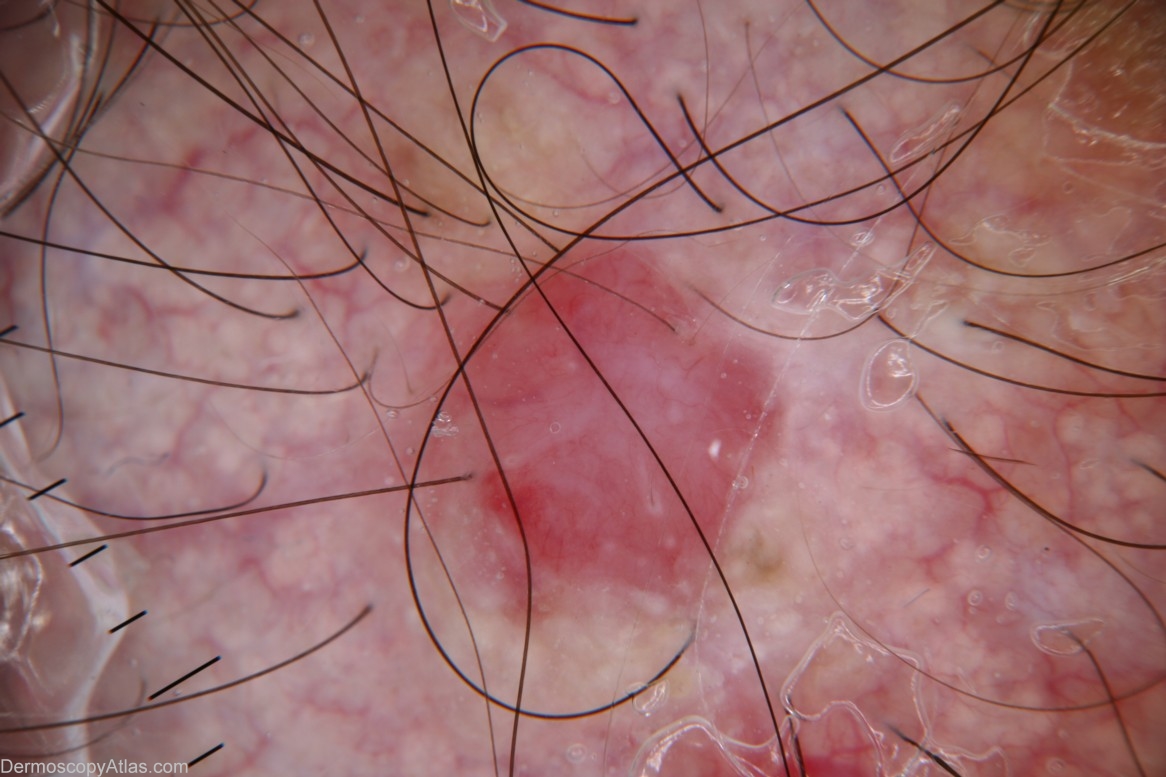

Description: Dermoscopy - This lesion is apigmented and structureless. The only dermoscopic features are a distinctive cherry colour and a few fine blood vessels